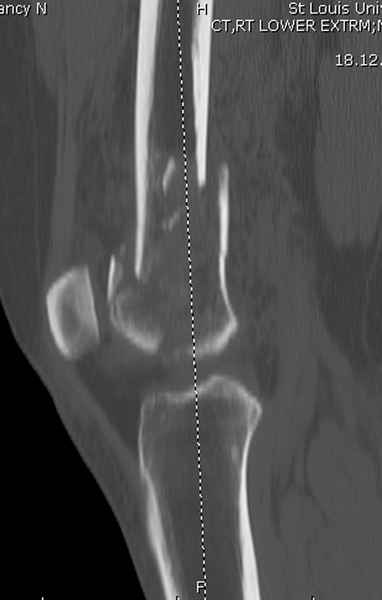

При наличии различных имплантов, любые варианты: слева (полу) открытым - мининвазивным, а справа закрытым интрамедуллярным методом, его считаем более чем приемлемым для фиксации данных переломов.

Проксимальная и дистальная блокировка, независимо от техники введения штифта, ретроградно или антеградно, гарантирует сращение сегментарных переломов бедра без укорочения. Штифты диаметром 12 мм с блокировкой сверху и вниз двумя шурупами выдерживают вес 75 кг больного, что позволяет раннюю профилактику контрактур.

Погоня за "красивой рентгенограммой" не всегда оправдана для фиксации кости, где имеется массивное мягкотканое покрытие. Если так уж хочется исправить положение кости, то при наличии ЭОП, большие костные фрагменты могут быть развернуты или приближены к основному фрагменту методом применения Joystick.

Главное в лечении сегментарных переломов - необходима осторожность при рассверливании канала, продвижение гибкого сверло через сегмент проводят без сверления, толканием, а то были случаи, когда весь сегмент крутился вместе со сверлом.